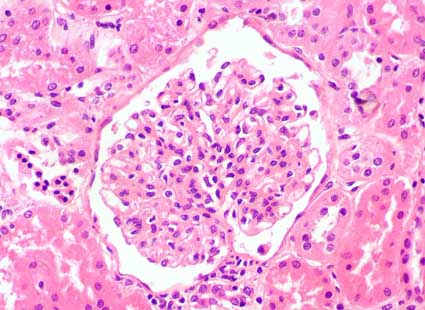

Figura 1.

En la mayoría de glomérulos hay proliferación mesangial

leve o moderada (H&E, X400).